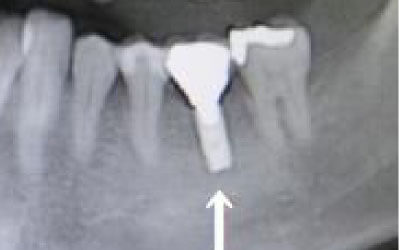

骨が薄い場合、そのままインプラントを行うのはお勧めできません。

ただし、事前に骨を増やす治療を行ったり、インプラントと同時に骨を増やす治療を施したりすることで、インプラントは可能です。

今回のご質問ですが、抜けた部分の骨が薄いなどの理由で「インプラントはできない」と言われた可能性があります。

前歯はもともと骨が薄く、歯が抜けると時間の経過とともにさらに骨が痩せてきてしまうので、インプラント治療の難易度が高い場所です。

ただ結論からお話すると、インプラント治療は可能です。

なぜなら、もし仮に骨が薄くても、骨の治療によって厚みが増せば、安全にインプラント治療が行えるからです。

1)インプラント治療を行う前に、骨の治療が必要かもしれません。

2)骨の治療から始めると、その分、治療期間が長くなります。

3)骨の治療は、通常のインプラント治療よりも難易度が高いため、経験の豊富な先生やインプラント認定医のいる歯科医院で治療を受けることをお勧めします。

4)骨の状況をしっかり把握するためにも、CT撮影が必須となります。